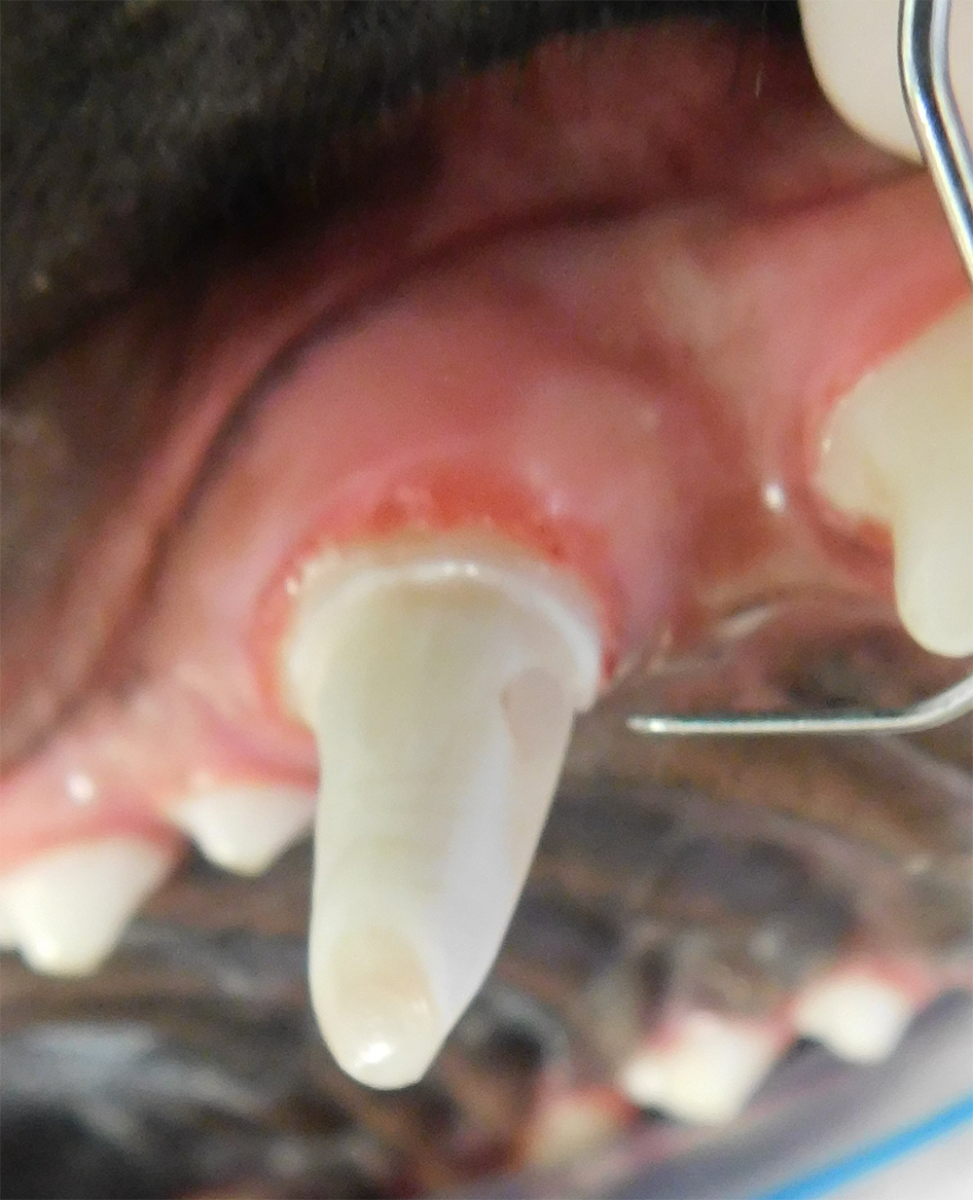

Tooth Resorption

Tooth resorption is a disease process where the body begins to break down the adult tooth. It is widely known to occur in cats but can also occur in dogs. In cats these lesions are thought to be inflammatory, while in dogs they can be more of a replacement resorption process. These lesions can be very painful and should be treated, generally with extraction depending on the type of resorption that is occurring. The disease can be progressive and affect many teeth over several years. It is important to have regular checkups and yearly dental cleanings to monitor for these lesions.